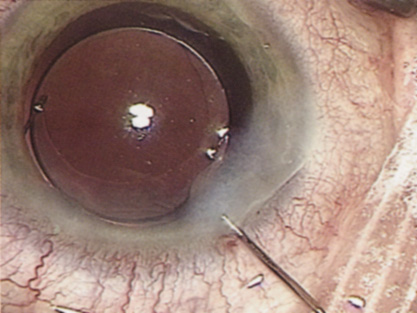

Capsulorrhexis can be performed with a cystitome, capsulorrhexis forceps, or combination-type instruments. Regardless of which instrument is used, several principles can help the surgeon successfully complete capsulorrhexis. It is important to maintain the anterior chamber, because making the chamber shallow increases tension on the zonules and causes the tear to run peripherally. The authors recommend the use of a viscoelastic agent for maintaining chamber depth and, of course, for endothelial protection. Therefore, if the tear begins to run peripherally, the surgeon should redeepen the anterior chamber before attempting to redirect the tear. Additionally, folding the capsule margin can aid the surgeon in redirecting the tear more accurately (Fig. 10).

Fig. 10. The capsulorrhexis tear is more easily redirected by folding the capsule over, in advance of the tear.